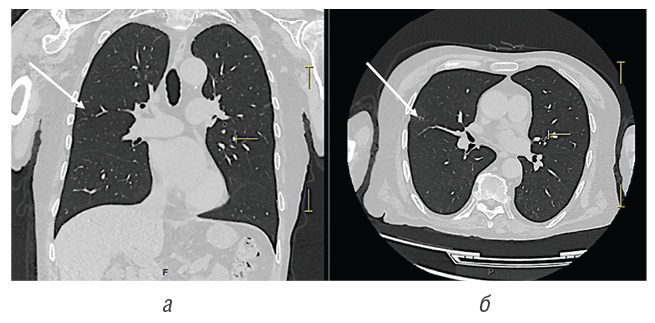

Инструментальные исследования: компьютерная томография (КТ) органов грудной клетки (рис. 5), в верхних долях обоих легких участки фиброза, в том числе типа «матового стекла», очень низкой интенсивности, объемные образования и участки патологической плотности в паренхиме легких и средостении не выявлены. Мультиспиральная компьютерная томография (МСКТ) лицевого скелета (рис. 6) — перфорация перегородки носа, неравномерное утолщение слизистой оболочки нижних отделов верхнечелюстных пазух.

Fig. 5. CT scan of the chest. Coronal view (a) and axial view (б) showing areas of fibrosis in the upper lobes of both lungs